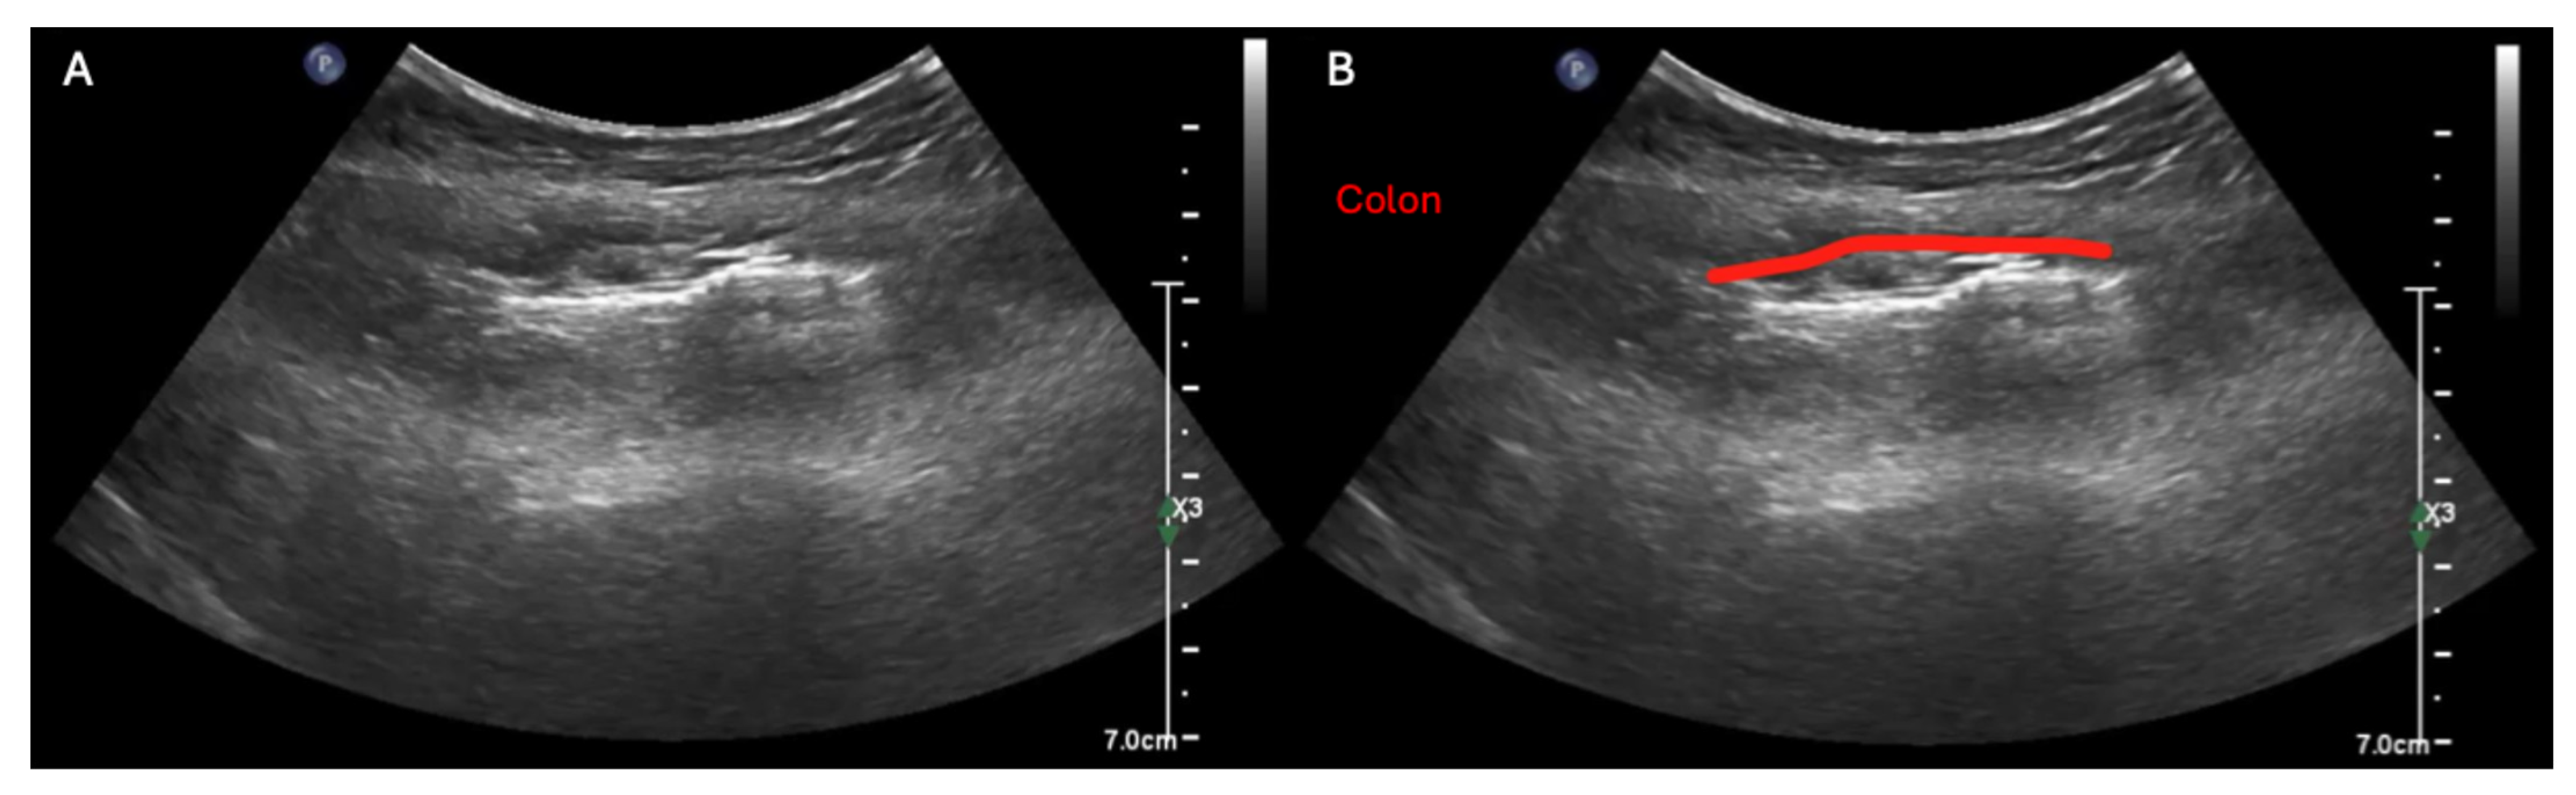

In contrast to obstructive small bowel processes, large bowel dilation can be difficult to definitively rule in with ultrasound alone. This is because the colon (red line) typically appears air-filled whether it is functioning normally or distended, and thus its lumen usually cannot be visualized in its entirety even in cases of severe colonic dilation [15], as shown in this unlabeled (A) and labeled (B) example of the sonographic findings in severe colonic ileus (see also Supplementary Video S6 for dynamic examples of these sonographic findings). So although a few case reports have described ruling in colonic obstruction with ultrasonography alone [16,17,18], in our experience, large bowel dilation more commonly manifests on ultrasound as diffuse acoustic shadowing within the abdomen with inability to visualize the full lumen of any segment of underlying bowel, which is a rather non-specific finding [5]. Thus, in any patient with abdominal distension, large bowel dilation should be included on the differential if ultrasonography reveals acoustic shadowing throughout the abdomen with inability to see the lumen of the underlying bowel [5]. Further, while POCUS cannot always differentiate small versus large bowel with certainty, several heuristics can be helpful: (i) within the abdomen, the small bowel tends to be centrally located, whereas the large bowel tends to lie peripherally and (ii) the upper limit of normal diameter of the small bowel, colon, and cecum grossly follows the classical 3–6–9 (cm) rule, so bowel that is 3–5 cm in diameter and fluid-filled is much more likely to be dilated small bowel than normal colon because (as mentioned previously) the air found in normal colon usually prevents visualization of the colonic’s entire lumen under either normal or abnormal circumstances [5].